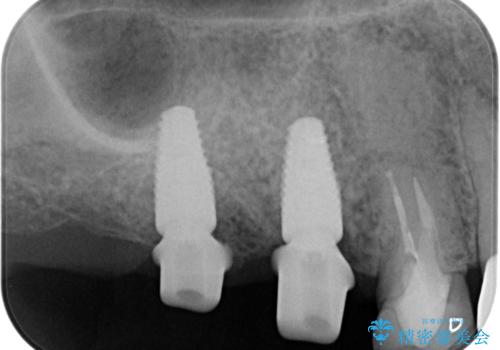

より清掃性の高い、チタン製カスタムアバットメント、審美製・強度に優れるジルコニアインプラントを用いたインプラント治療を計画します。

- 88万円(インプラント×2・チタンカスタムアバットメント×2・ジルコニアクラウン×2・仮歯×2)費用は治療当時の料金となります